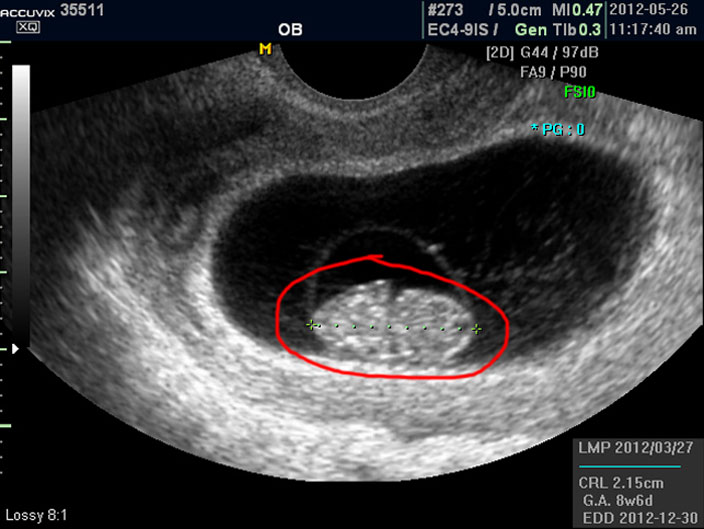

우선 첫번째로 보이는 사진에서 가운데 하얗게 보이는 것이 태아입니다.

우측이 머리 부분이고 좌측이 몸통 부분이며 초기 임신에서는 아기 머리가 몸통의 반정도로 상당히 큰 상태입니다.

따라서 하얗게 보이는 태아 주변의 검은 부분은 양수입니다.

태아의 크기는 우측 하단에 실제 크기가 나와 있지만 아래 사진에서 빨갛게 표시한 부분의 안에 보이는 눈금이 1cm입니다.